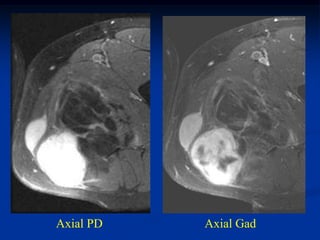

Case #1192

23 year female with

angiolipoma anterior

to hip joint

Axial T-1 MRI

Sagittal T-1 MRI

Coronal T-1 MRI

Case #1192 23 yearfemale with angiolipoma anterior to hip joint